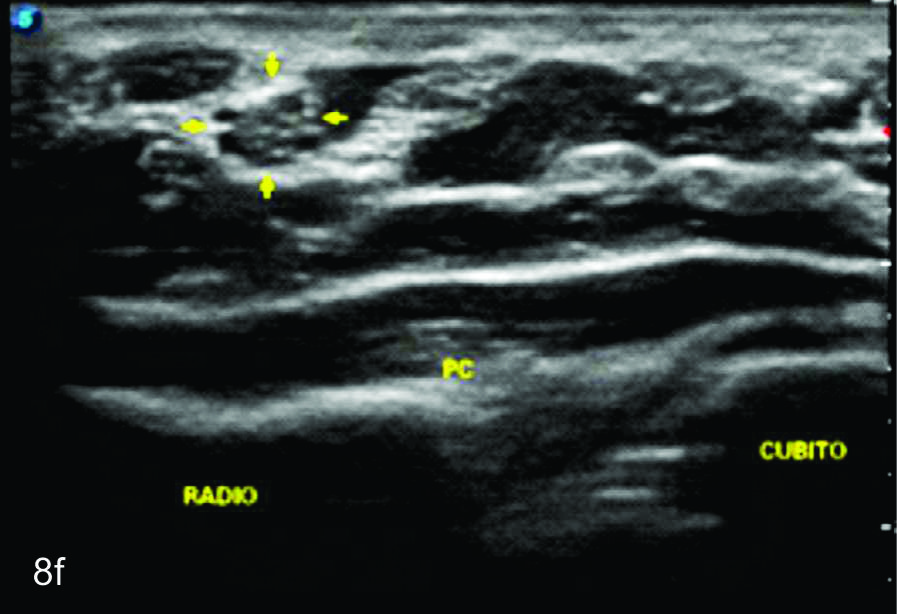

Serie de cortes axiales del nervio cubital desde su origen a nivel del hueco axilar hasta su terminación a nivel del canal de Guyon. Se identifica el mismo señalado por flechas amarillas y con las letras NC. AH-arteria humeral, PC- músculo prondador cuadrado, P- hueso pisciforme, Línea roja- ligamento anular del carpo, Línea amarilla- túnel de Guyon, Flecha azul- Arteria cubital-. A-tercio distal antebrazo, B- canal de Guyon.

Figura 8

Nervio mediano

Serie de cortes axiales del nervio mediano desde su origen a nivel del hueco axilar hasta el sector distal del antebrazo previo a su ingreso al túnel del carpo. Se identifica el mismo señalado por flechas amarillas y con la palabra mediano. AA-arteria axilar, VA- vena axilar, AH- arteria humeral, VH- vena humeral, VB- vena basilar, AC- ateria cubital, VC- vena cubital, BA- músculo braquial anterior, PR- músculo pronador cuadrado, FS- músculo flexos superficial, FP- músculo flexor profundo, PC- músculo pronador cuadrado. A- axila, se identifica el nervio superfical a la arteria axilar, B- tercio medio del brazo en canal bicipital medial, lateral a la arteria humeral, C- codo, medial al tendón distal del bíceps braquial y a la arteria humeral luego de cruzarla, superficial al músculo braquial anterior, D-antebrazo sector cefálico, entre las dos cabezas del pronador redondo, E- tercio medio del antebrazo, entre los músculos flexor superficial y profundo F- tercio distal antebrazo, superficial al pronador cuadrado.